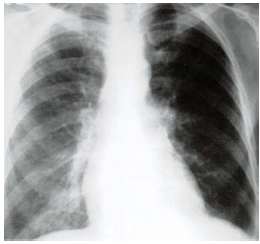

Assinale a alternativa que apresenta o sinal observado no raio x: